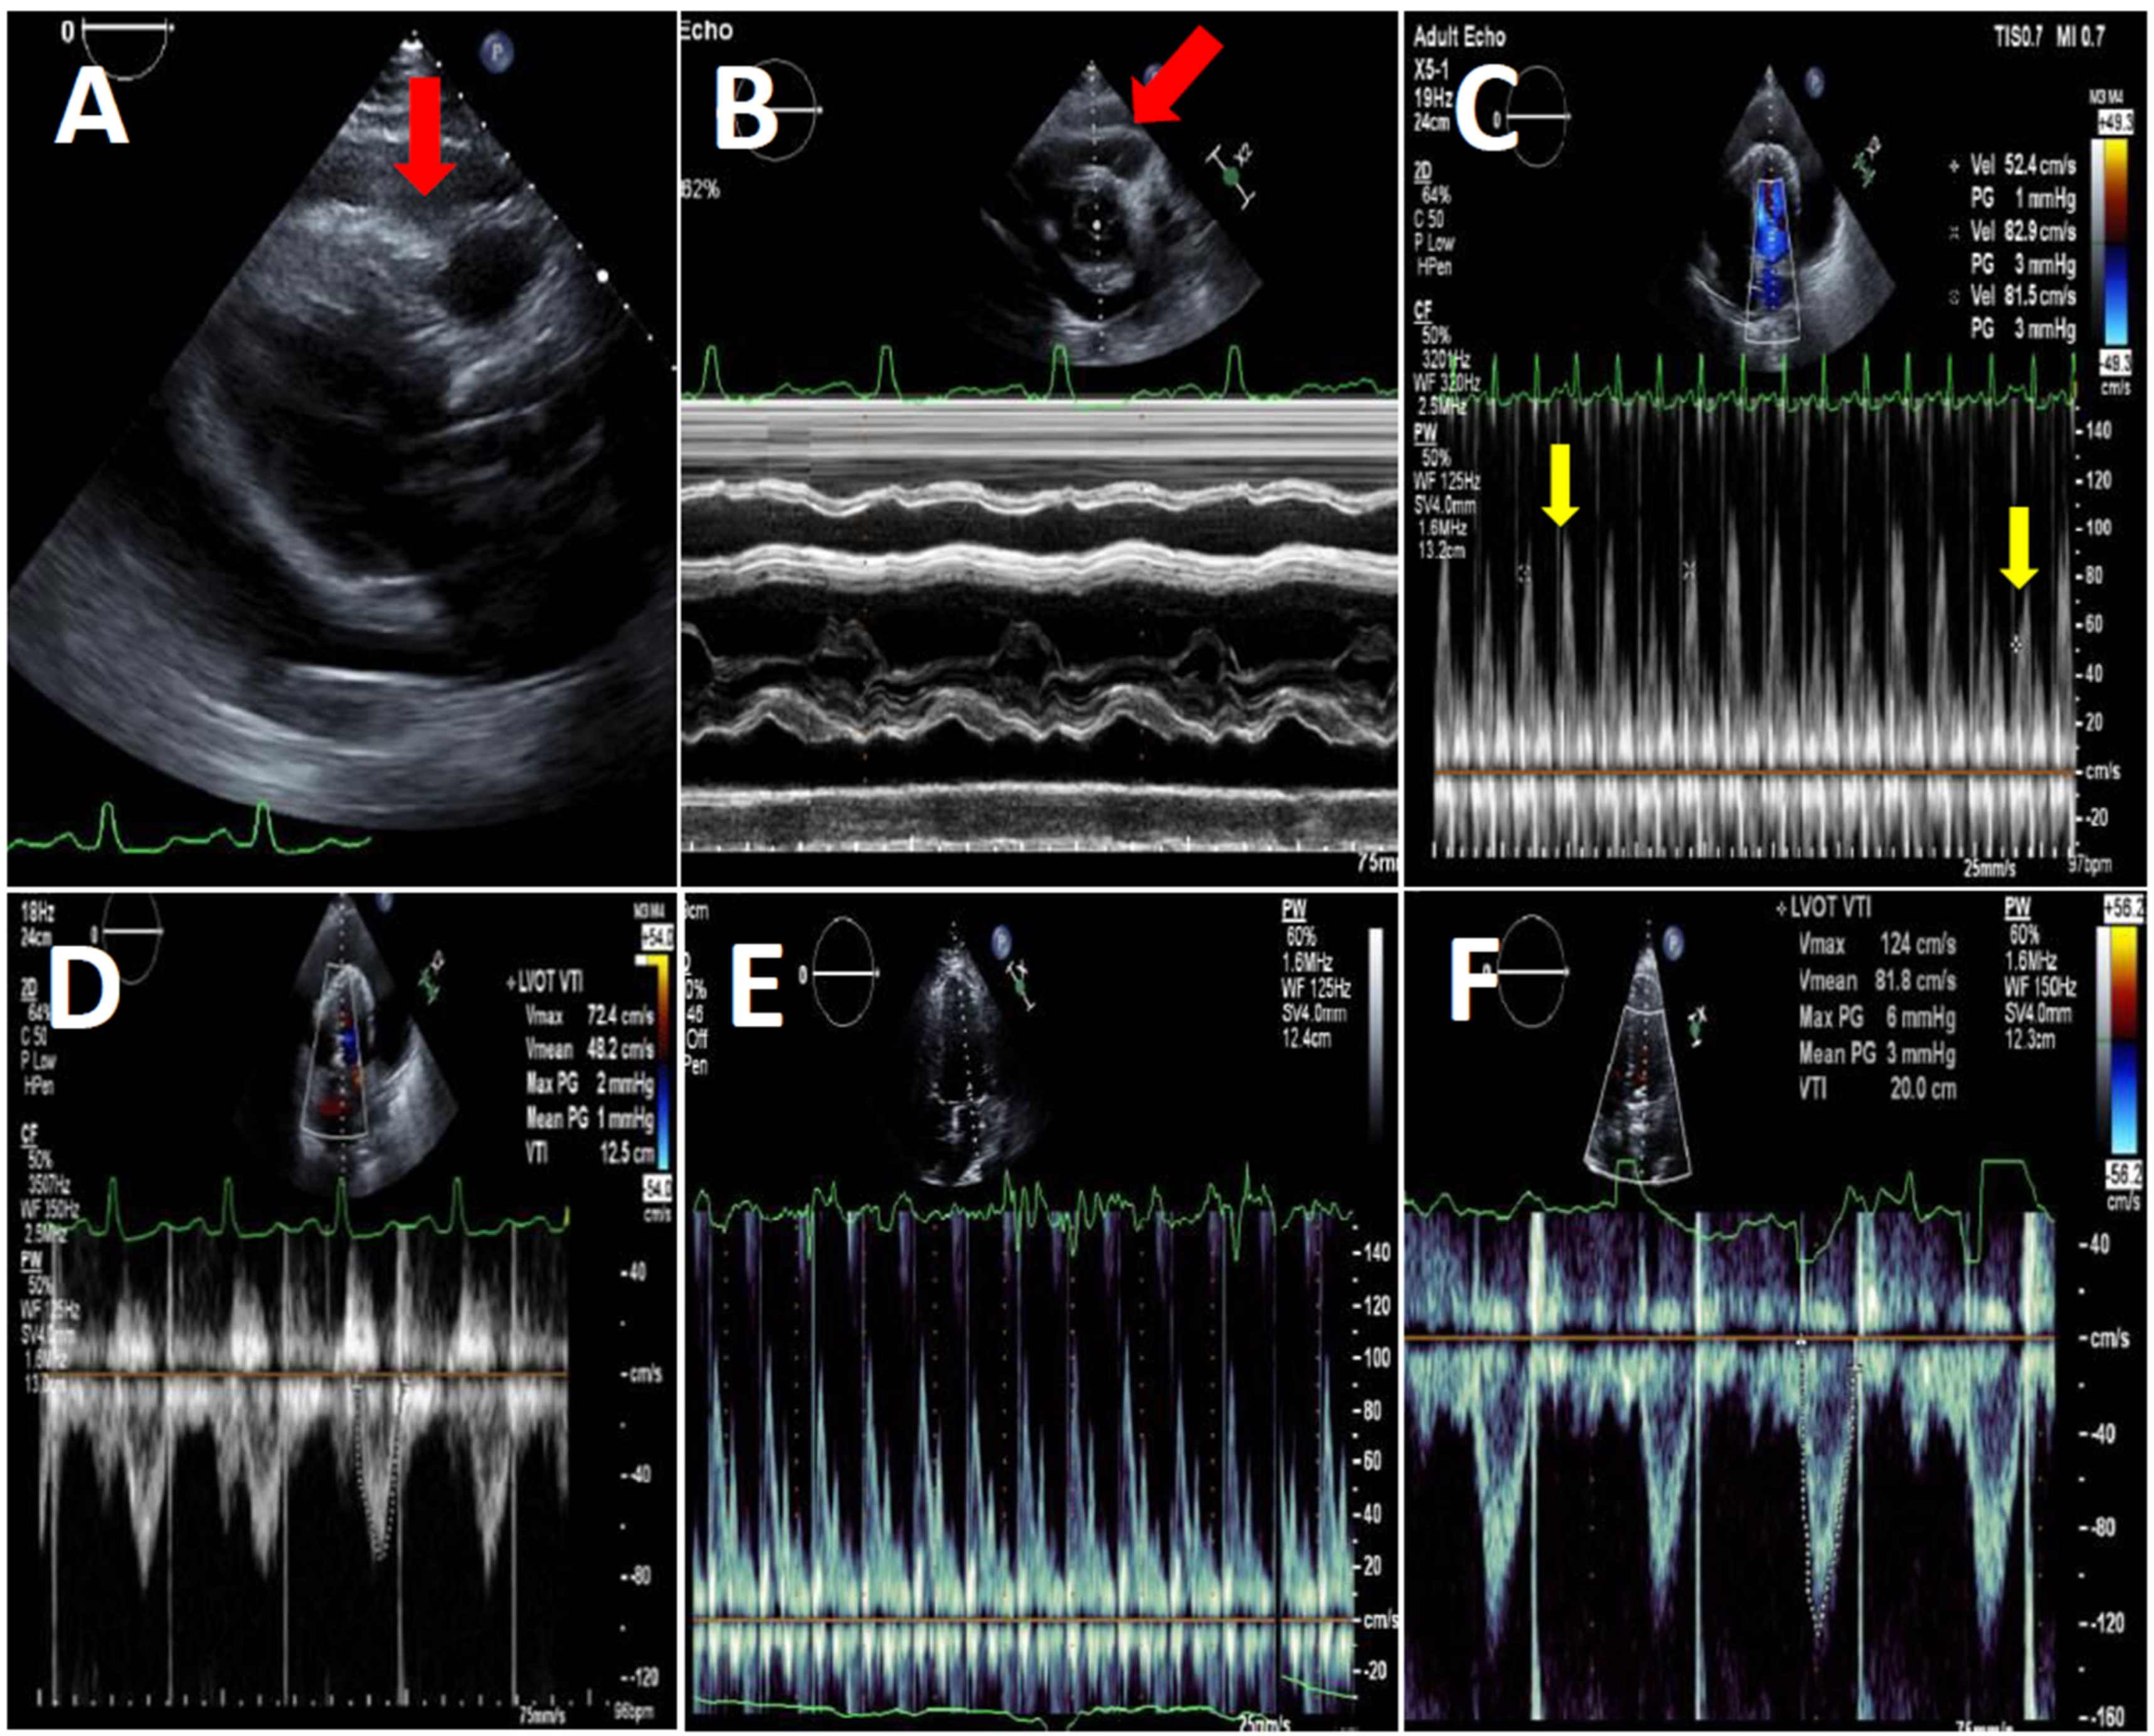

Left ventricular function and effusion size were determined by echocardiography (Figure 2). All studies were performed by experienced sonographers and were interpreted by senior cardiologists specialized in echocardiography [8,9]. All studies were performed with the VIVID E3 95 Ultrasound device manufactured by General Electric and were held following the standard protocol of the American Society of Echocardiography guidelines.

Transthoracic echocardiography of a COVID-19 patient before (panels (A–D)) and after pericardiocentesis (panels (E,F)). (A)—Parasternal long axis view, diastolic RV free wall collapse (red arrow) due to high pressure in the pericardial space, due to a large circumferential pericardial effusion. (B)—Short axis view M-Mode at the level of the aortic valve showing diastolic collapse of the RV free wall (red arrow). (C)—Apical 4-chamber view PW Doppler of the mitral flow showing respiratory variations between beats (yellow arrows). (D)—Apical 4-chamber view PW Doppler of the left ventricular outflow tract systolic flow showing low VTI, indicating low stroke volume. (E)—Apical 4-chamber view PW Doppler of the mitral flow showing normalization of mitral flow pattern. (F)—Apical 4-chamber view PW Doppler of the LVOT systolic flow showing normal VTI, indicating normal stroke volume.